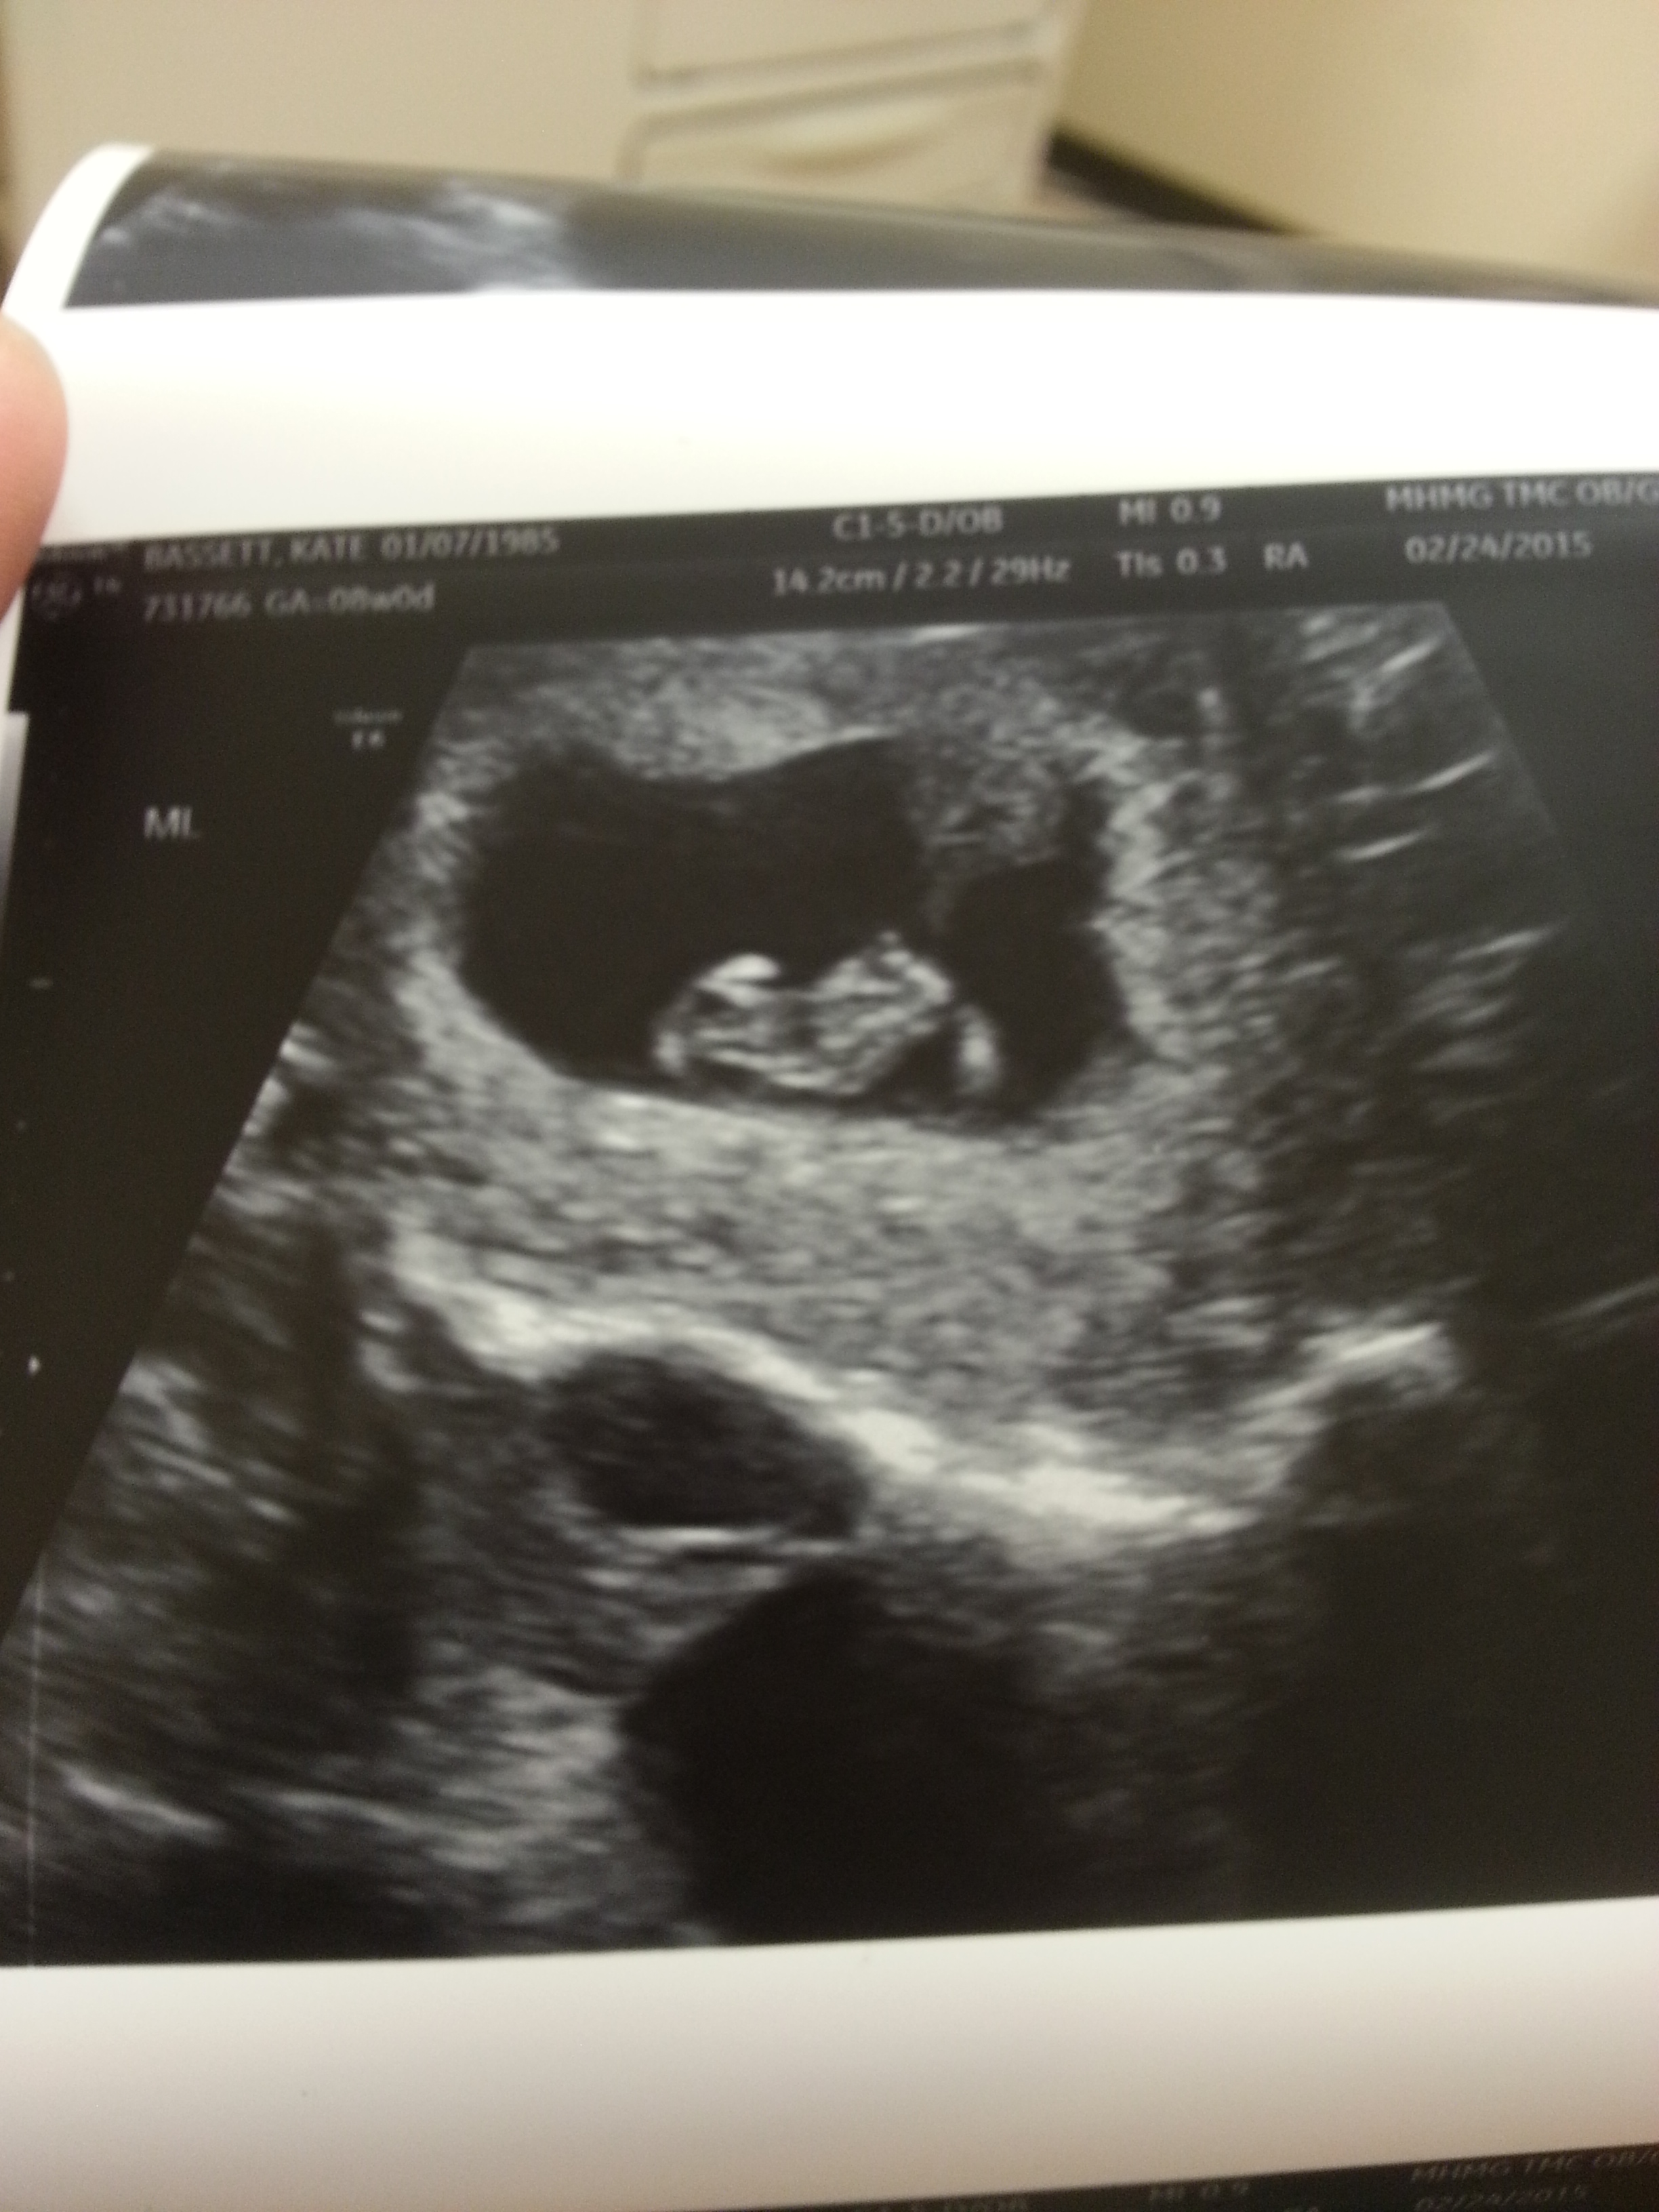

• Little baby Bassett measuring at 8w5d when I had my appt a week ago!